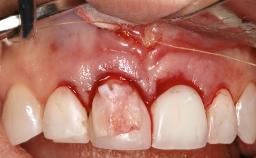

Paolo Casentini and Matteo Chiapasco present a case in which the peri-implant defect was not suitable for a fully regenerative approach. It involves implant removal, use of a CAD/CAM customized titanium mesh in the grafting phase, and placement of new implants. A 62-year-old woman was referred for consultation regarding her implant-supported prosthesis replacing teeth 14 to 16. The patient’s main concern was pain and recurrent swelling in the right posterior maxilla. The patient also reported difficulty and discomfort when brushing the area. The patient reported she had been treated in another country, where she had received three implants in combination with sinus-floor augmentation for the replacement of the posterior maxillary teeth three years earlier. The patient indicated “endodontic complications” to be the reason for the extraction of the teeth.